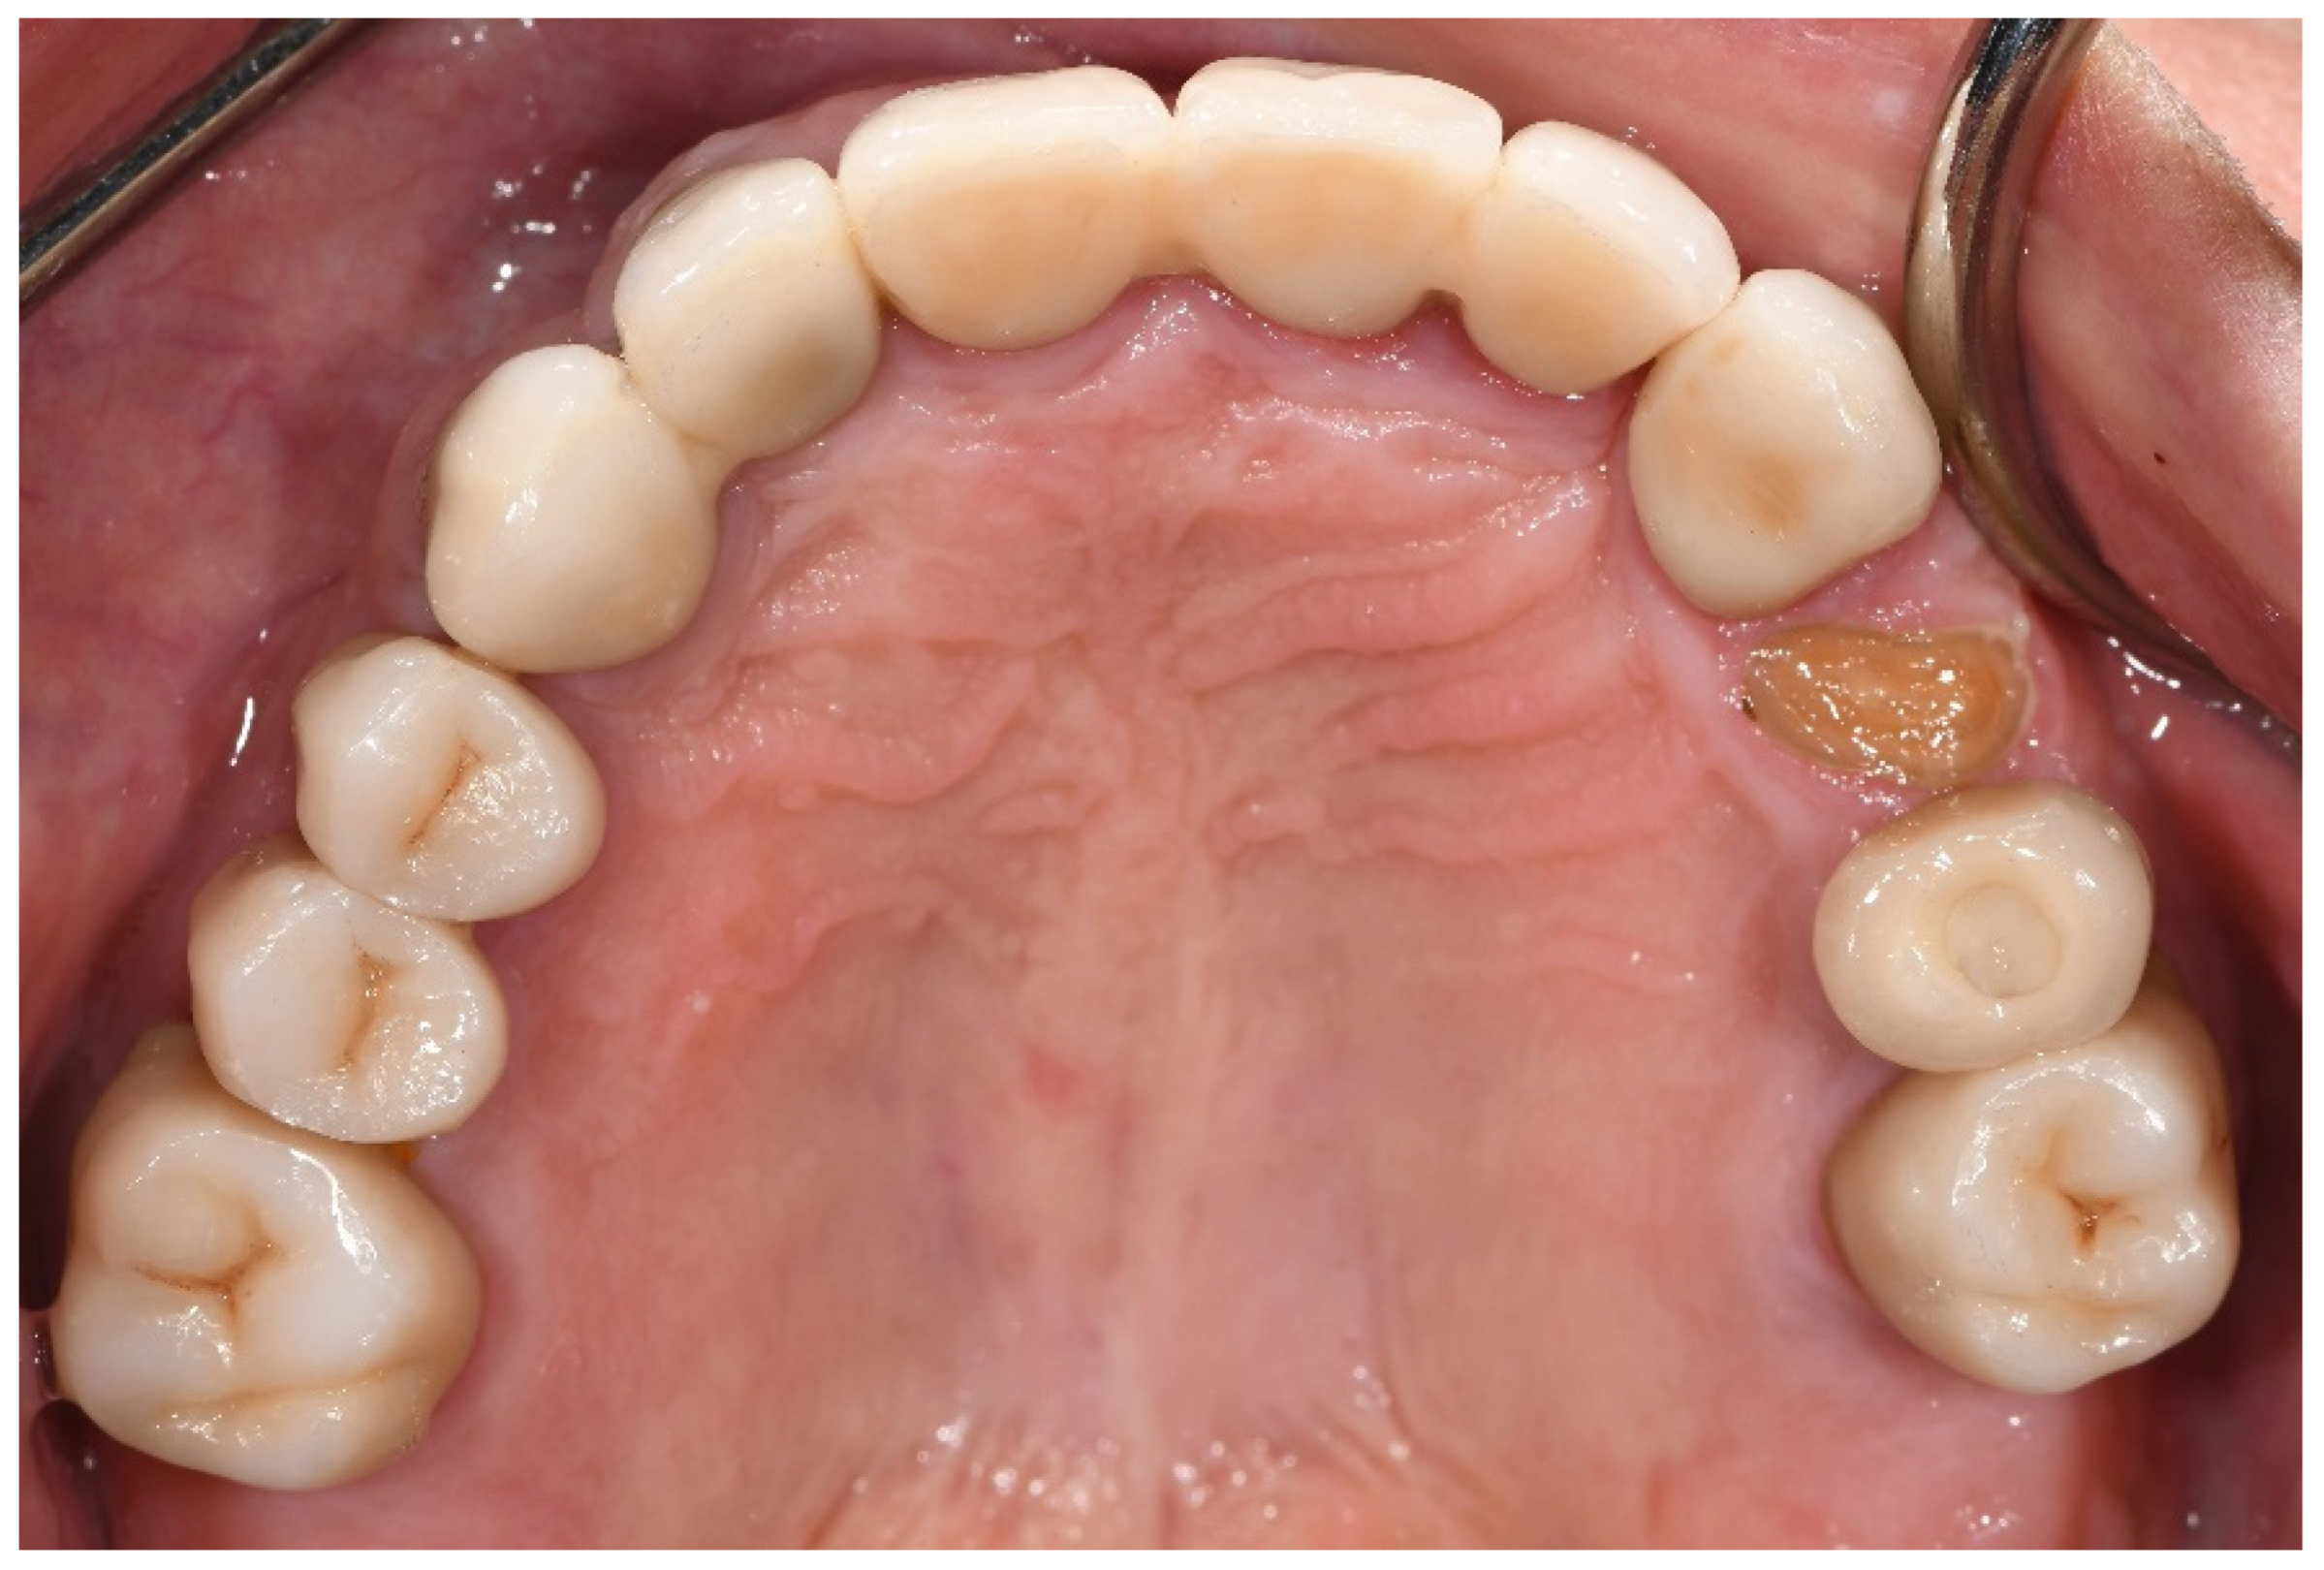

With regard to technical complications, the rate of porcelain chipping on the incisal edge of the veneered monolithic restorations was significantly higher in the bruxer group than in the non-bruxers (p = 0.045). In all cases, porcelain chipping required only polishing (grade 1); therefore, the restorations were not replaced (Figure 2).

Figure 2. Porcelain chipping on the incisal edge of the veneered monolithic restoration in the upper left central incisor, three years post-cementation. Repair required only polishing.